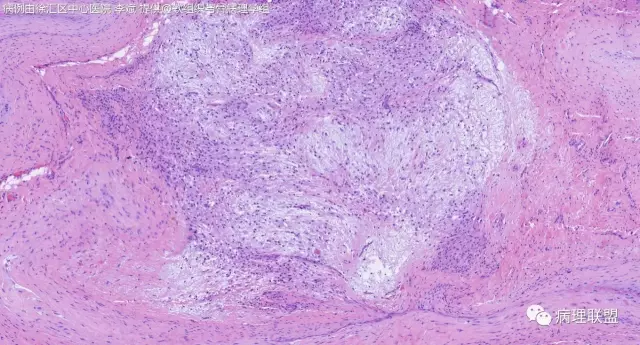

关节旁粘液瘤,肿瘤中间明显有腱鞘囊肿结构,又发生在关节处!强烈提示为关节旁粘液瘤,部分病例可以呈分叶结构!平时多加观察腱鞘囊肿囊壁常可见粘液变性!范围一广就成粘液瘤样。

取材时我以为是腱鞘囊肿,片子出来这样@周泉